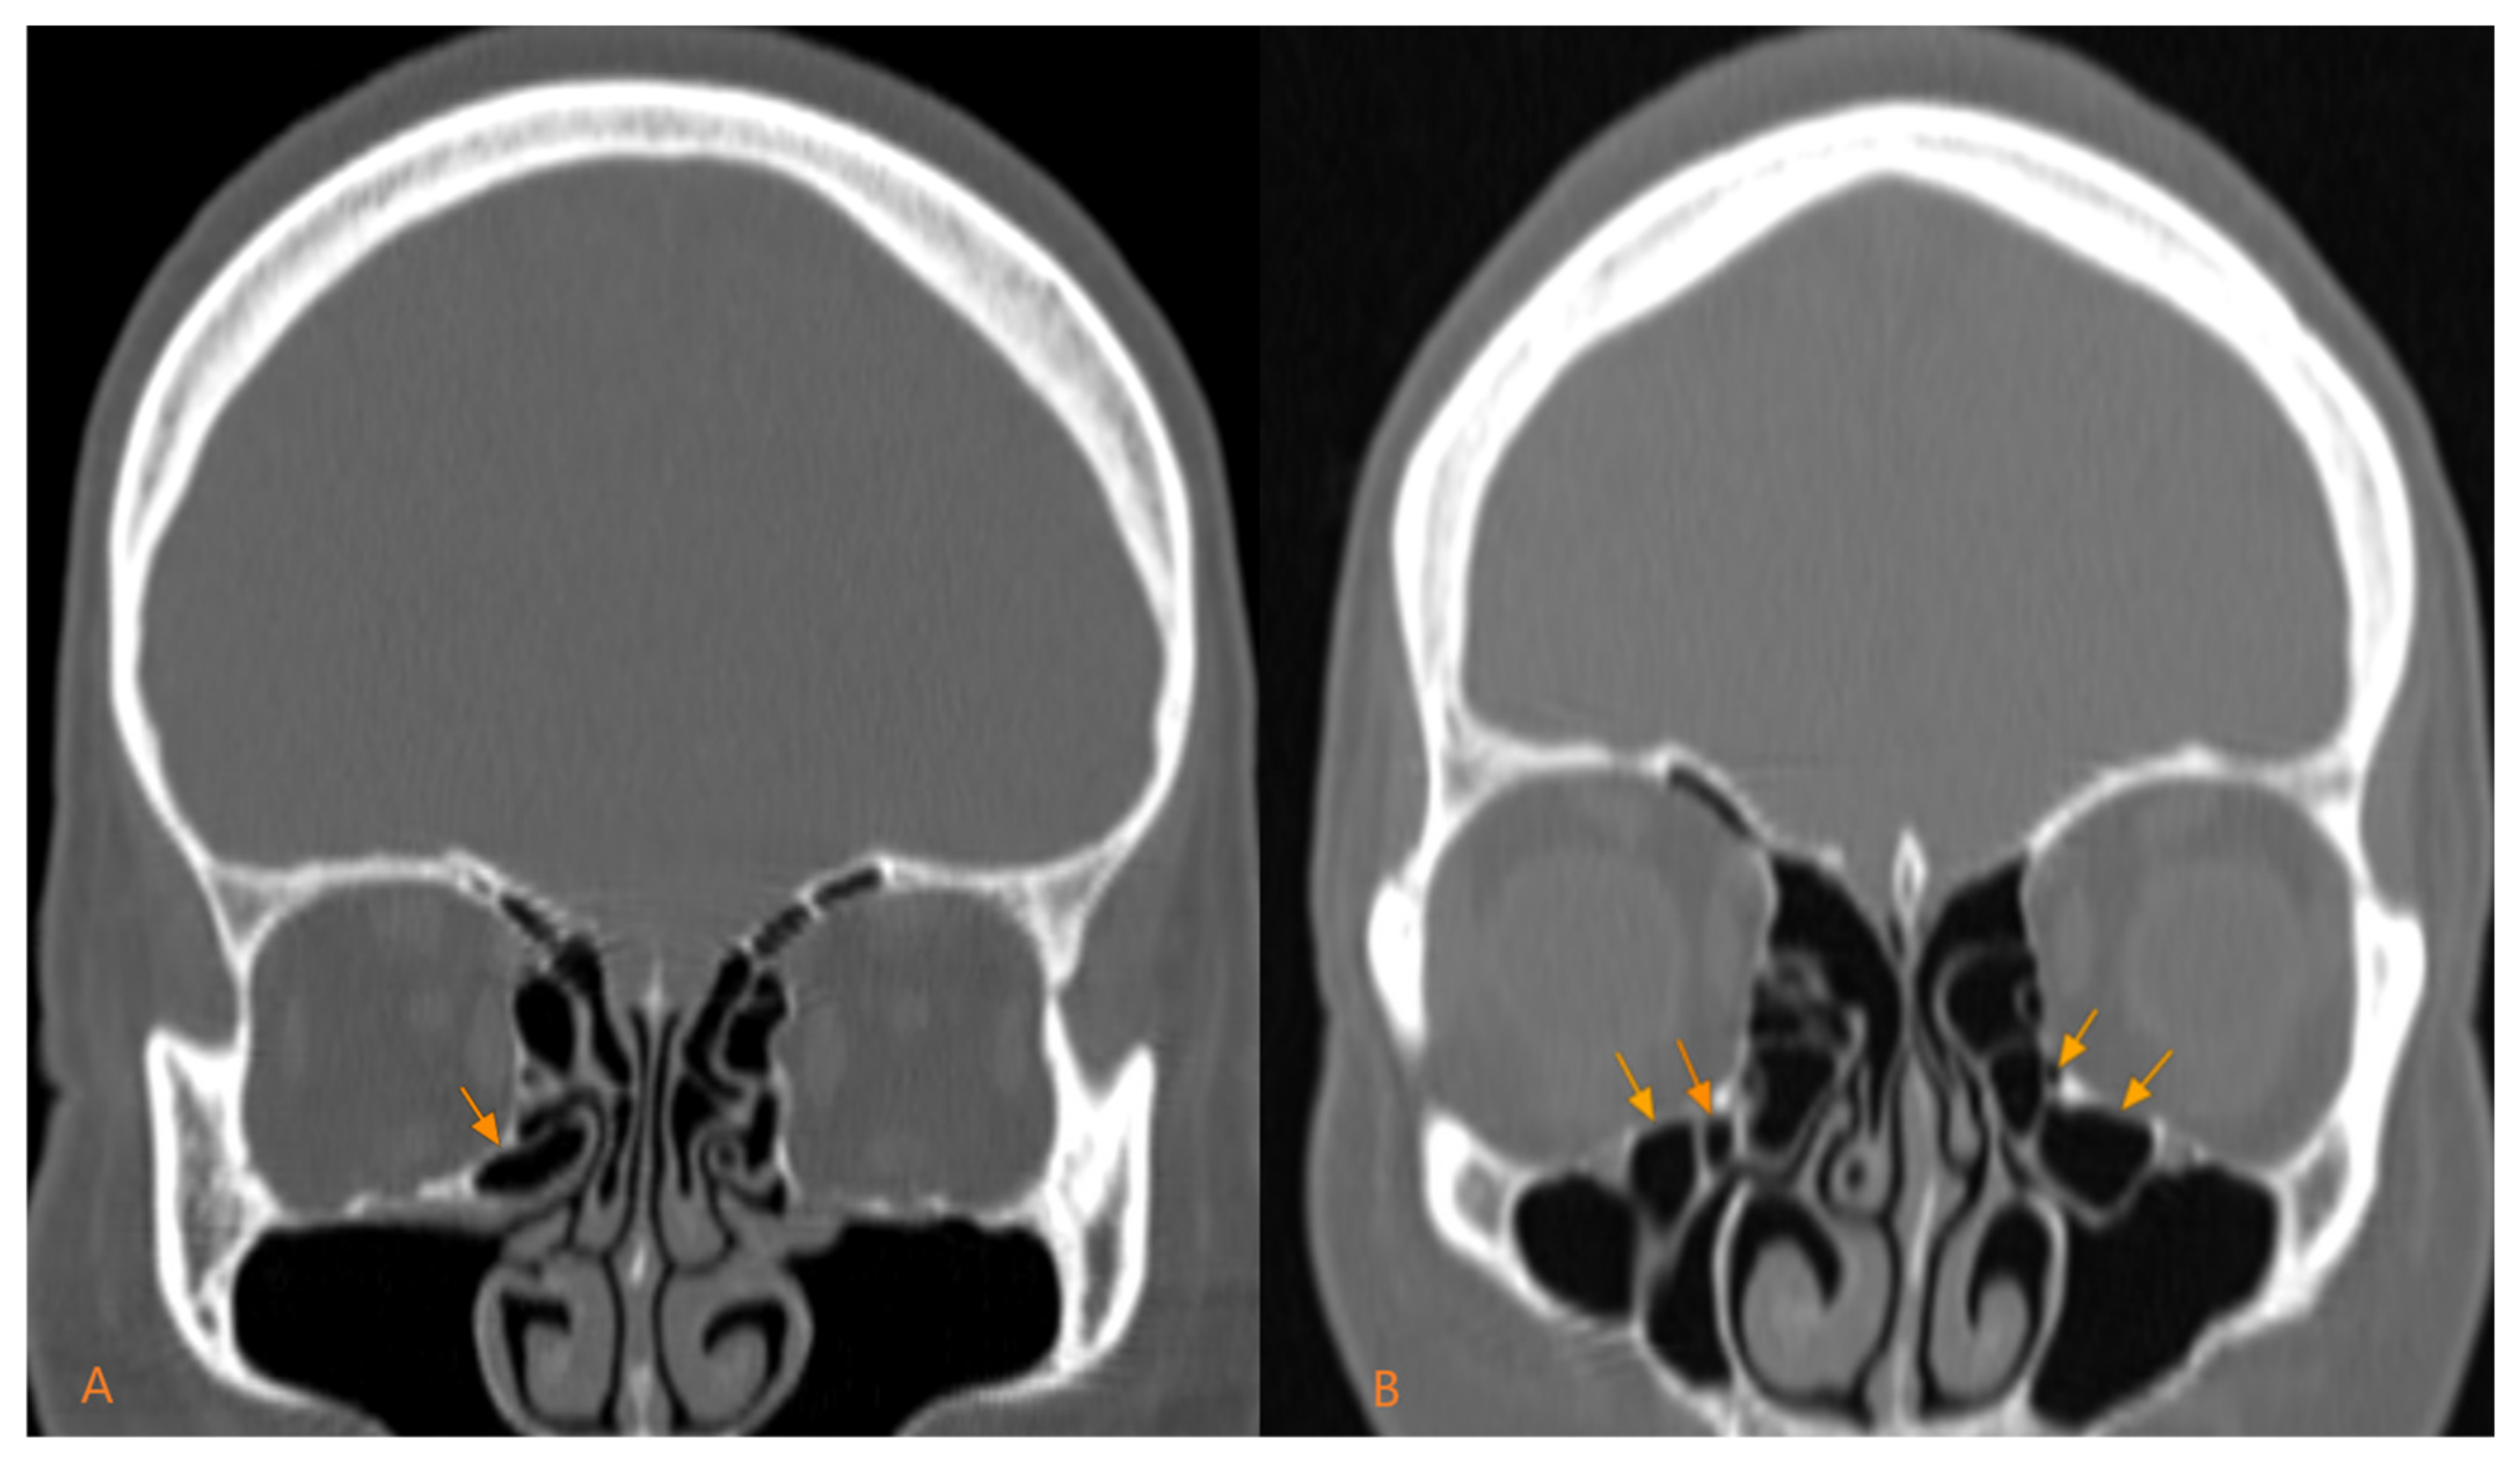

3.4. Haller Cells: Morphologic Types According to Gender and Location

Regarding the morphological type, the predominant type is the unilocular type, namely 66.19% (141 out of 213), compared to the multilocular type, which is 33.81% (72 out of 213) (Figure 2). Their prevalence by gender follows the same distribution, in men, the unilocular type is predominant, present in 78 out of 122 cases (63.93%), compared to the multilocular type, present in 44 out of 122 cases (36.06%). In women, the unilocular type represented 69.23% of cases (63 out of 91) compared to the multilocular type, which represented 30.76% of cases (28 out of 91). The statistical analysis did not show significant differences between the two genders for the morphological types, p = 0.418 (Table 4).

The unilocular morphological type is predominant in both unilateral (37 out of 43) and bilateral (104 out of 170) forms. The multilocular type is a minority both in bilateral locations (66 out of 170) and in unilateral locations (6 out of 43). Regarding the distribution of morphological forms according to location, a statistical significance is reached (p = 0.002), so that we can conclude that the unilocular type predominates (Table 5).

Figure 2. Morphological types of Haller cells: (A) unilocular; (B) multilocular.